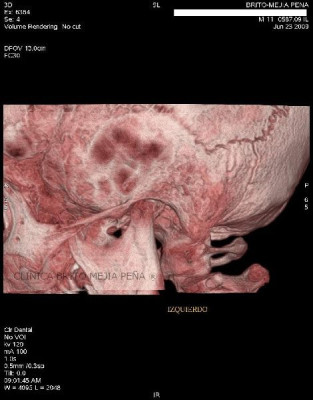

Envíado por BMP Imágenes Diagnósticas

BMP Imágenes Diagnósticas